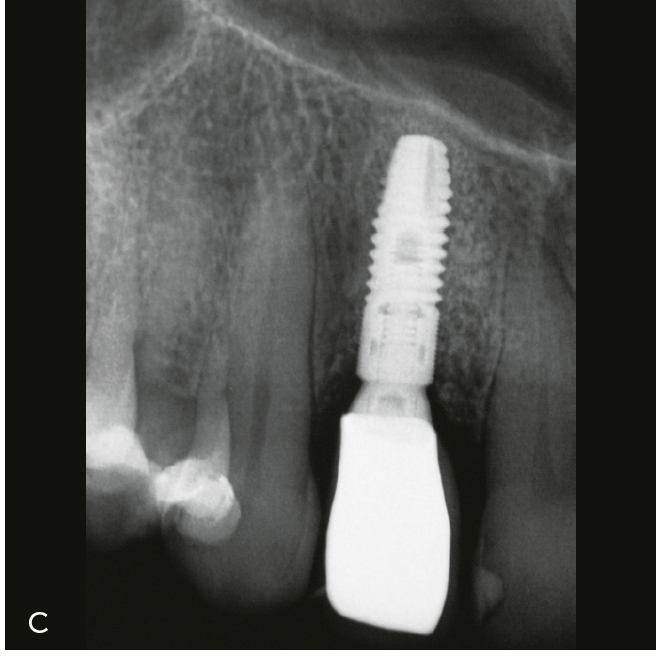

Abb. 3a bis h Falldokumentation mit Zustand nach Implantation und lateraler Augmentation alio loco: a) klinische Ausgangssituation mit Fistelung vestibulär in der Region 12; b) klinische Parameter (PI=Plaque Index 1-3, ST=Sondierungstiefe, MR=Mukosarezession, KM=keratinisierte Mukosa, BOP=Bleeding on probing, SUPP=Suppuration); c) radiologische Ausgangssituation mit initialem periimplantären Knochenabbau; d) operativer Zugang; e) Defektdarstellung nach Entfernung des periimplantären Entzündungsgewebes; f) Defektaugmentation mit einem Gemisch aus Eigenknochen und xenogenem Knochenersatzmaterial; g) Kollagenmembran; h) das aus dem Gaumenbereich entnommene Bindegewebstransplantat (BGT).